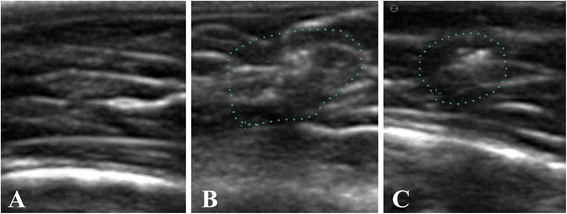

Methods: Twenty-four rats were divided into a control group, Notexin group (7 and 14 days) and a Notexin + EPI group. To induce muscle injury, Notexin was injected in the quadriceps of the left extremity of rats. Pro-inflammatory interleukin 1-beta (IL-1beta) and tumoral necrosis factor-alpha (TNF-alpha) were determined by ELISA. The expression of receptor peroxisome gamma proliferator activator (PPAR-gamma), vascular endothelial growth factor (VEGF) and vascular endothelial growth factor receptor-1 (VEGF-R1) were determined by western-blot.

Results: The plasma levels of TNF-alpha and IL-1beta in Notexin-injured rats showed a significant increase compared with the control group. EPI® produced a return of TNF-alpha and IL-1beta values to control levels. PPAR-gamma expression diminished injured quadriceps muscle in rats. EPI® increased PPAR-gamma, VEGF and VEGF-R1 expressions. EPI® decreased plasma levels of pro-inflammatory TNF-alpha and IL-1beta and increased anti-inflammatory PPAR-gamma and proangiogenic factors as well as VEGF and VEGF-R1 expressions.